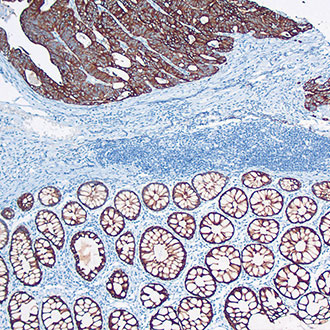

CDX-2

CDX-2 -